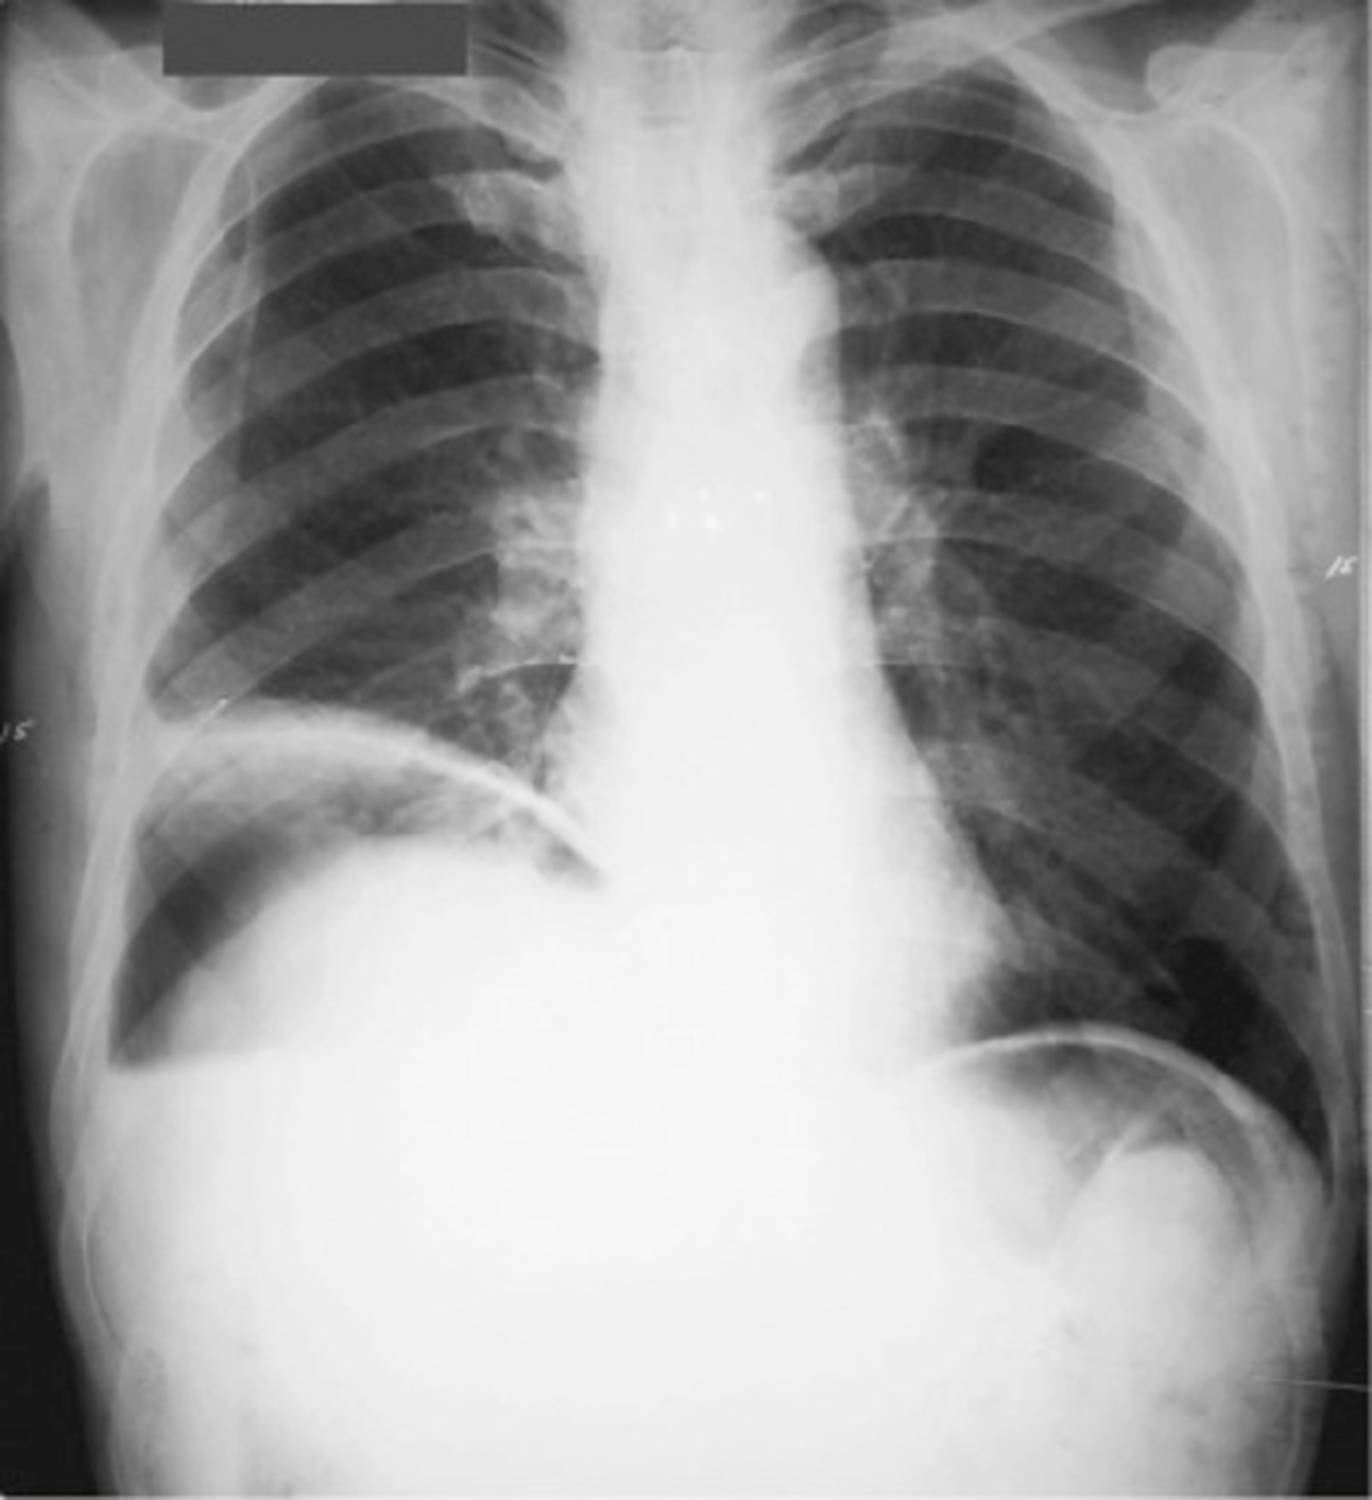

• Neumoperitoneo (aire debajo del diafragma, generalmente sobre el hígado).